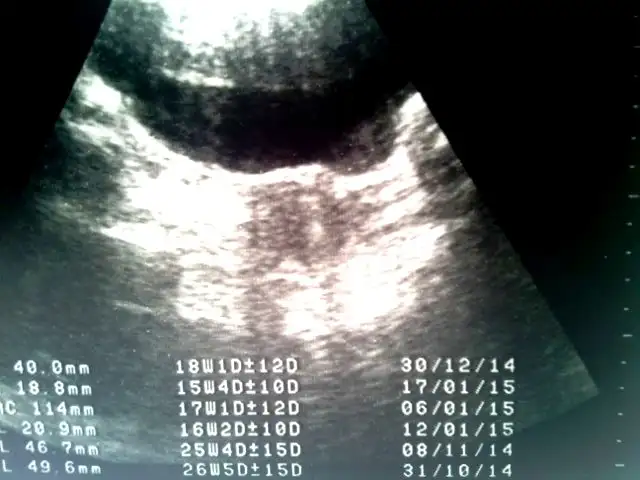

ultrason goruntum bılemedım ne oldugunu